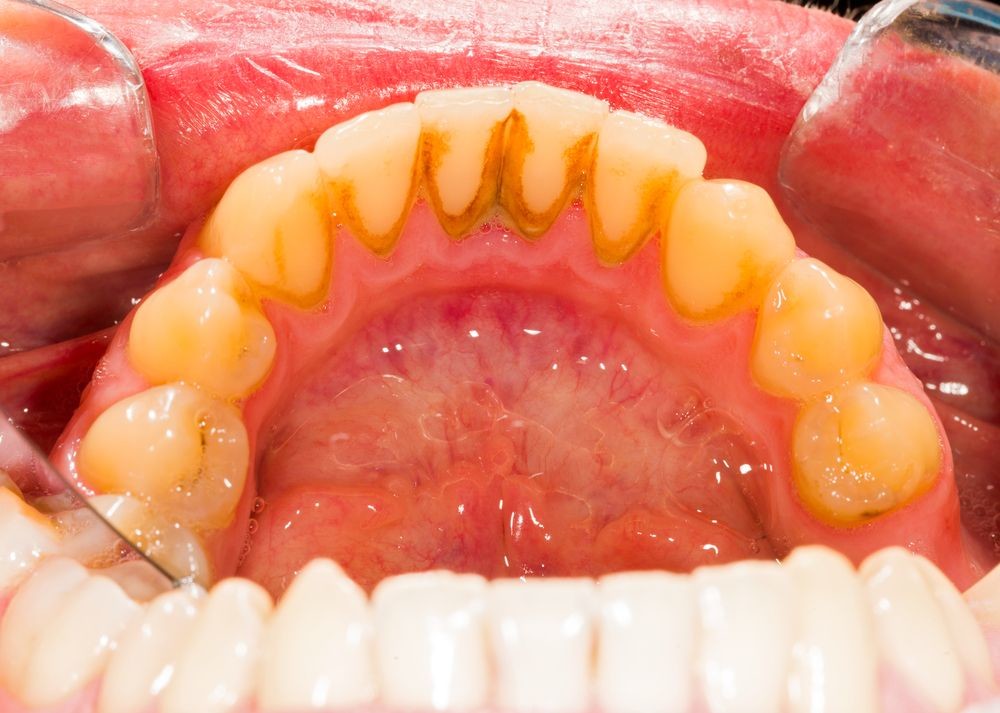

Frenulum In The Mouth

What Is A Frenum (Frenulum)?

In our mouth, most people have two groups of tissue called frenums found in and around the gums and teeth. It is a piece of really soft tissue that appears as a thin line between the gums and lips. You can find it on the top and the bottom of your oral cavity. There’s also a frenum that extends along the bottom of the tongue and connects to the bottom of the mouth just behind the teeth. Different people have different frenums. It can vary in length and thickness.

Types Of Frenum

There are two basic types of frenums in your mouth:

Labial frenum – This type of frenum is placed in the front of your mouth between the upper lip and gum. His counterpart is positioned between the lower gum and the lower lip. If there is an issue with this type of frenum, it can change the way your teeth grow in and can influence your dental health. Particularly it can pull your gums away from a tooth revealing the root.

Lingual frenum – This type of frenum is located between the floor of your mouth and the base of your tongue. It comes in different sizes and sometimes it can limit the movement of your tongue. This means frenum is tight, and we call this condition: tongue-tie. If this happens, it can affect the way the tongue moves in your mouth. This problem is especially annoying for babies because it makes it hard for a baby to feed properly.

Possible Problems With Frenum

The main purpose of a frenum is to give the lower and upper lip, as well as the tongue proper support and more stability in your mouth. If you suffer from an oversized frenum, it can lead to various problems that can affect your teeth, gums, and mouth.

· disruption of the healthy growth of your upper two front teeth, which may cause a gap

· the gap formed between front teeth

· receding of gum tissue away from the root of the teeth and revealing the tooth root.

What Is A Frenectomy?

A frenectomy is a procedure that removes your frenum tissue. Luckily, most people feel instant benefits after a successful frenectomy. This routine procedure normally takes a couple of minutes and is pretty simple to perform. Although it is still a surgery, the patient will be released in no time with minimal pain and discomfort in the following days. When performing a frenulum surgery the surgeon numbs the area and creates an incision to free it from being so tight or sometimes he removes it completely.

Stitches are only required depending on the size and severity of the frenum tissue. Modern “surgery” technique uses laser surgery, making less tissue damage, and scarcer bleeding for improved healing time.

Frenectomy may be used as a preventative measure, especially with young children without permanent teeth. It is important to point out that frenectomy won’t make your already spaced teeth come together. That is why it is recommended to complete any orthodontic treatment before you get a frenectomy.